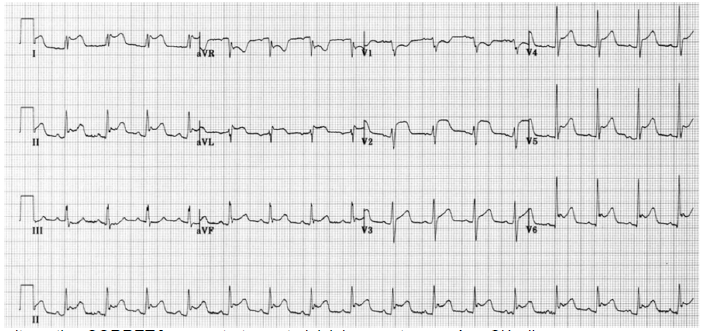

Dona Ana Cláudia, 32 anos, previamente saudável, apresenta história de dor precordial de início há 24 horas, de forte intensidade, a qual piora com a respiração, deglutição e ao se deitar. A dor irradia para o pescoço e ombro (em especial para as bordas do músculo trapézio). Relata que a queixa é constante e não se relaciona com esforço, além de não aliviar com dipirona 500 mg. EF: eupneica, normocorada e afebril. Pressão arterial: 142x82 mmHg, FC: 106 bpm, FR: 15 rpm, temperatura axilar de 37,1ºC e saturação de 95% em ar ambiente. Os marcadores de necrose (0- 6-9 horas) apresentaram discreta elevação. Eletrocardiograma e raios X do tórax, a seguir.

Assinale a alternativa CORRETA para o tratamento inicial proposto para Ana Cláudia.